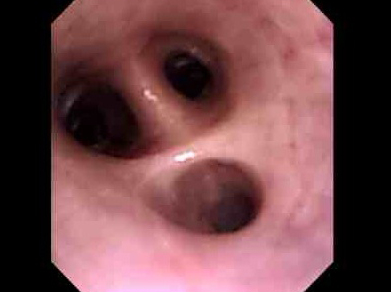

慢性的にくしゃみ、鼻水がでているわんちゃんの鼻腔内観察および生検を行いました。

口から内視鏡をいれ、咽頭部、鼻腔内と進めていきます。

病変部です。血液の混じった粘性のある鼻汁。粘膜には炎症所見が確認できます。

この子は生検により鼻から出血しないよう、滅菌ブラシにて生検を行ないました。